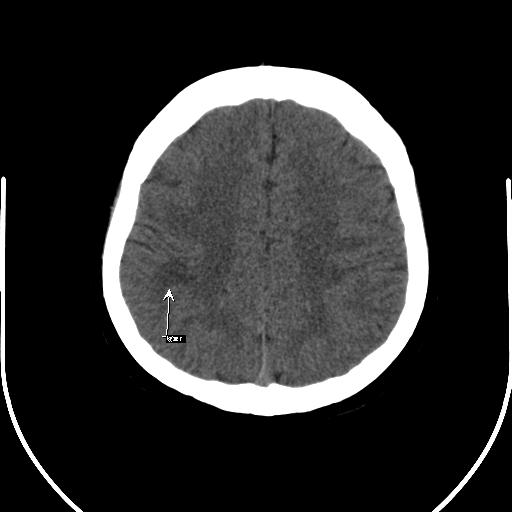

以下是引用mlxq3086在2007-8-27 13:35:00的发言:[br]单凭平扫无法诊断,请结合增强了解!